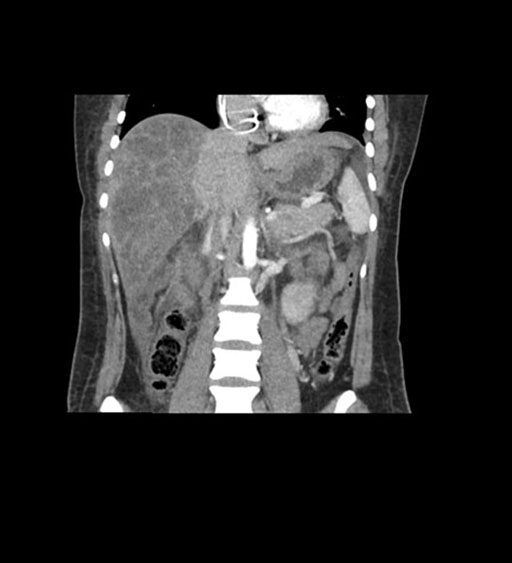

Coronal Arterial